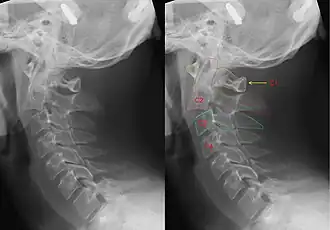

Hangman's fracture

| CT scan of hangman's fracture | |

Hangman's fracture is the colloquial name given to a fracture of both pedicles, or partes interarticulares, of the axis vertebra (C2).[1]